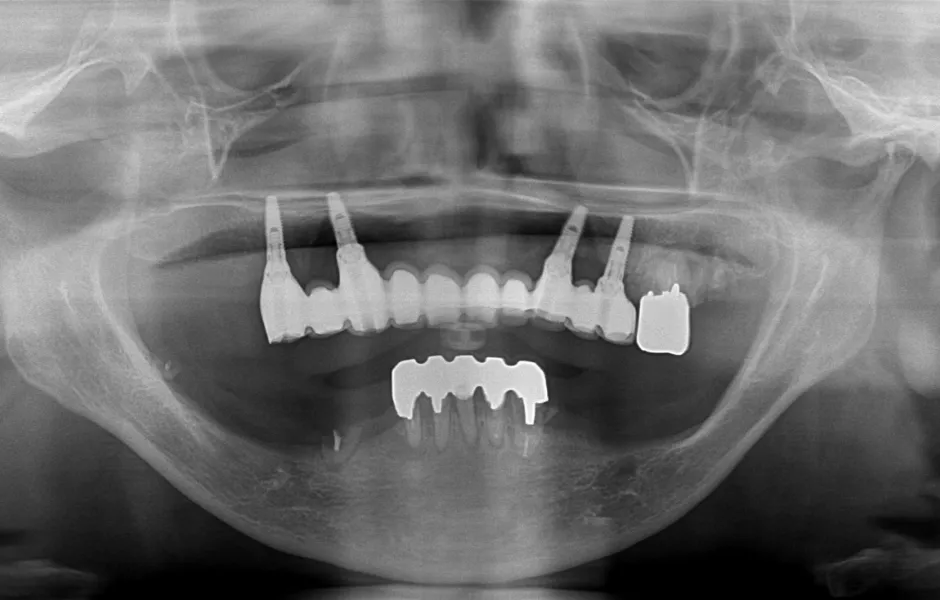

インプラント治療

失った歯を補う方法の1つで、インプラントが歯根の代わりを果たすことで天然歯に近い噛み心地を再現します。当院ではサージカルガイドを使用することで、より精密な埋入を可能とし、術後の痛みや腫れを軽減しています。機能性だけでなく審美性も回復します。

オールオン4・6

歯をすべて失っている方にインプラントを4~6本埋入して、連結した人工歯を支える治療法です。手術回数と埋入数が少ないので、患者さまの体への負担と費用を軽減できます。